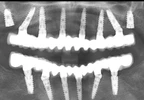

2007 yılı Kasım ayından beri İstanbul Ataşehir’deki Kliniğinde İmplantoloji, Ağız ve Çene Cerrahisi, Ağız içi Kemik Nakli Cerrahileri, Kalça Kemiği (iliac kemik), Kemik Greft Nakilleri ve Estetik Diş Hekimliği konularında çalışmalarına devam etmekte,hastalarına hizmet vermektedir.

Doktora Tezi -İleri İmplant Cerrahisi Kemik Greftleri Uygulamaları

Ağız diş ve çene cerrahisi